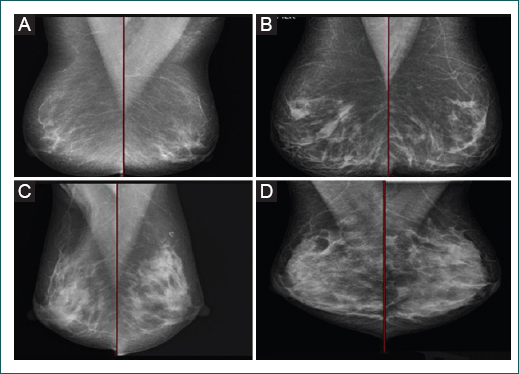

Según la clasificación BI-RADS (Breast Imaging Reporting and Data System), la densidad mamaria puede presentar cuatro patrones: adiposo (A), tejido fibroglandular disperso (B), tejido heterogéneamente denso (C) y tejido extremadamente denso (D).12 La densidad mamaria se asocia directamente con los antecedentes familiares de cáncer de mama, uso de terapia hormonal combinada y alto estatus socioeconómico, e inversamente con mayor edad, paridad y peso.13

Estudio observacional, transversal y retrospectivo, en el que se recolectaron 2187 reportes de mujeres a quienes se realizó mastografía digital de diagnóstico o escrutinio en tres instituciones: 1426 mujeres del hospital privado Sanatorio Español, 228 mujeres de consultorios privados y 533 mujeres del Hospital General de Zona Número 16 (HGZ#16) del Instituto Mexicano del Seguro Social, durante el periodo de enero de 2013 a marzo de 2017. En los gabinetes privados, el 60% de las mastografías realizadas eran de tamizaje y el 40% de diagnóstico; en el Sanatorio Español, el 80% eran de tamizaje y el 20% de diagnóstico; y en el HGZ#16, el 85% eran de tamizaje. Las mastografías las realizaron cinco radiólogos certificados por el Colegio Mexicano de Radiología e Imagen y certificados en mama, tres de ellos laborando en los sectores público y privado, y dos solo en el privado. Se utilizaron las siguientes unidades de mamografía digital: Gi0770 class 2017-11 (GIOTTO, IMS GIOTOO), Selenia® Dimensions® FFDM-SD (Hologic®, EMSOR) y Mammommat 3000 Nova (Siemens, Everx). La clasificación de densidad mamaria usada fue la del American College of Radiology en el BI-RADS 5.ª edición12 (Fig. 1).